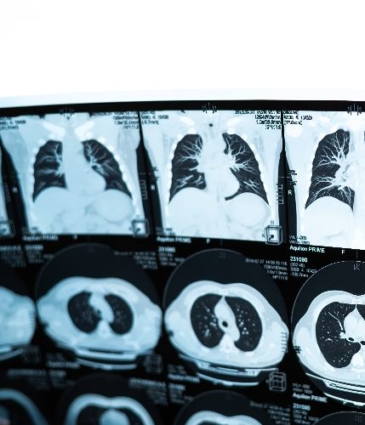

Advanced imaging refers to specialised, high-resolution scans used to assess the heart and blood vessels in greater detail than basic diagnostics allow.

At Dr Sen’s clinics, these include cardiac MRI, CT coronary angiography, and echocardiography with Doppler analysis. These tests help visualise heart anatomy, blood flow, valve function and coronary artery disease. They are often used to confirm a diagnosis, guide treatment decisions, or monitor progress in patients with known or suspected cardiac conditions. All imaging is performed in partnership with top-tier diagnostic centres for maximum accuracy.